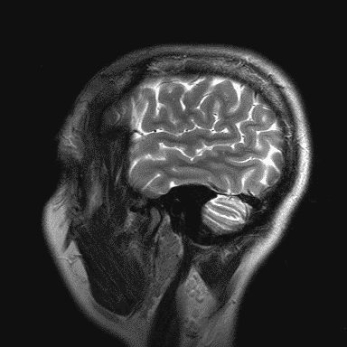

Действительно ли мозг работает на 10% и его возможности снижаются к старости.

Мозг - наименее изученный человеческий орган. Многие аспекты его работы остаются загадкой для ученых всего мира. Это рождает множество мифов, заявили в ЦГРБ Сызрани.